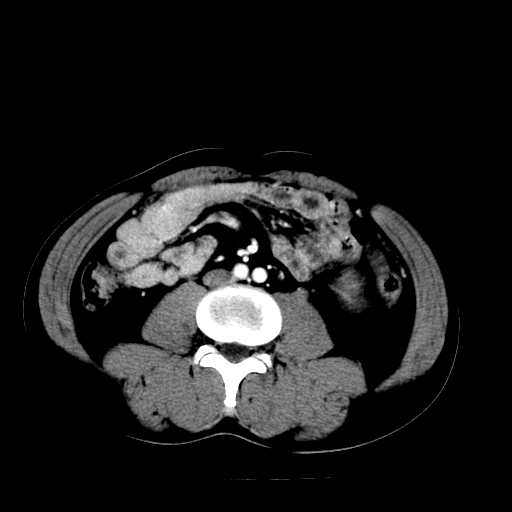

以下是引用天南地北在2007-4-30 13:36:00的发言:[br]支持慢性胰腺炎伴有假性囊肿

以下是引用andymaomao在2007-4-30 14:28:00的发言:[br]支持:1.慢性胰腺炎并假性囊肿形成可能;[br] 2.左肾形态稍增大,旋转不良。